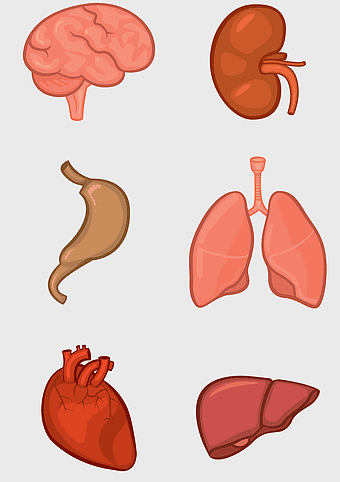

human internal organs illustration, heart and lung anatomy, kidney and liver diagram, brain and stomach structure, medical organ chart, human body systems visual, educational anatomy graphics -